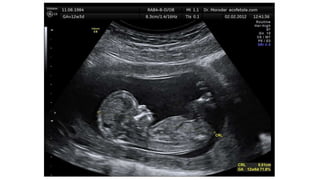

ECOGRAFIA

• Laecografía o ultrasonografía esun método diagnóstico que emplea ondas

acústicas de alta frecuencia (ultrasonidos) y obtiene imágenes de los

órganos internos al captar el ecode estasondas.

• Laecografía obstétrica seusapara diagnosticar la existencia de embarazo y

valorar la situación del embrión o el feto.